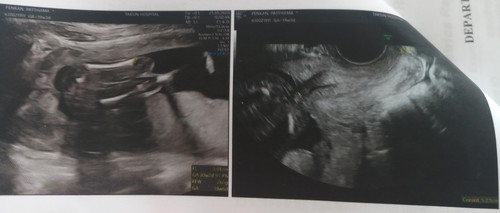

สอบถามค่ะเห็นเพศน้องไหมค่ะเป็น ช ญ ค่ะ

หมอบอกว่าน้องเอาตูดขึ้นค่ะ

ตามที่หมอบอกค่ะแม่ มองไม่เห็นเพศเลยค่ะ

บ้านนี้ซาว3รอบแร้วน้องยังไม่ให้เห็นเรยค่ะ